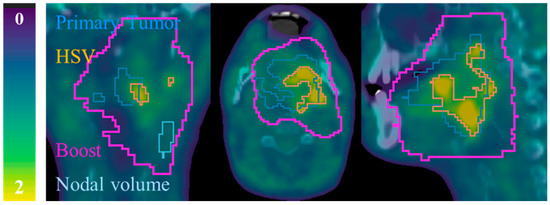

2.3. Segmentation

Appendix A. Automatic FMISO Segmentation Using the Parotid Contour from Radiotherapy Planning

- Firstly, CT from radiotherapy planning is co-registered with FMISO-image by the corresponding CT and contralateral parotid contour (Vparotid) is transferred to all FMISOs.

- Then, for each voxel of Vparotid the intensities derived from the tree FMISOs (W0, W2 and W5) were multiplied and voxels that resulted in zero were removed from the contour. This step took into account the possibility of having part of the Vparotid out of the FMISO image.

- Finally, the background (Bgparotid) was defined selecting the voxels with highest uptake until filling a volume of 6 mL. By focusing on higher uptake voxels, we could minimized the partial volume effect (PVE) given in voxels in the peripheral zone of the body and the co-registration error. Additionally, a volume of 6 mL permitted to minimize the PVE in the computation of SUVmean.